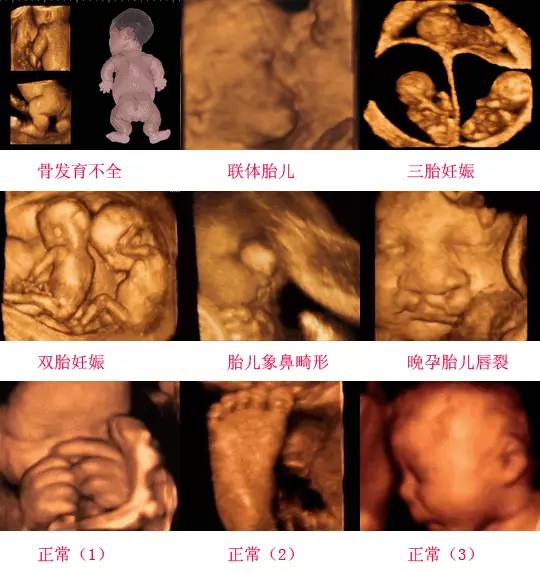

四維彩超是一種先進的醫(yī)學影像技術,通過實時觀察胎兒在母體內(nèi)的活動情況,為醫(yī)生提供了豐富的診斷信息,在四維彩超下,我們可以清晰地觀察到胎兒的蛋蛋(睪丸)的形態(tài)、位置和大小等特征,胎兒蛋蛋是男性生殖系統(tǒng)的重要組成部分,對于胎兒的生長發(fā)育具有重要意義。

在四維彩超下,胎兒蛋蛋呈現(xiàn)出特定的形態(tài)和外觀,通常情況下,胎兒蛋蛋呈現(xiàn)出圓形或橢圓形,表面光滑,內(nèi)部回聲均勻,隨著胎兒的發(fā)育,蛋蛋會逐漸增大,并呈現(xiàn)出明顯的性別特征,醫(yī)生可以通過四維彩超技術,對胎兒蛋蛋的大小、形態(tài)和位置進行評估,以判斷胎兒生殖系統(tǒng)的健康狀況。

四維彩超技術在評估胎兒蛋蛋發(fā)育方面具有重要意義,通過四維彩超,醫(yī)生可以實時觀察胎兒蛋蛋的形態(tài)、位置和大小等特征,了解胎兒生殖系統(tǒng)的發(fā)育情況,四維彩超還可以幫助醫(yī)生發(fā)現(xiàn)可能的異常情況,如睪丸未降、睪丸囊腫等,為及時采取治療措施提供依據(jù)。